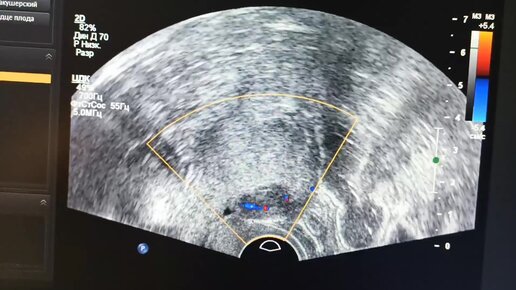

УЗИ начинающим врачам: миома